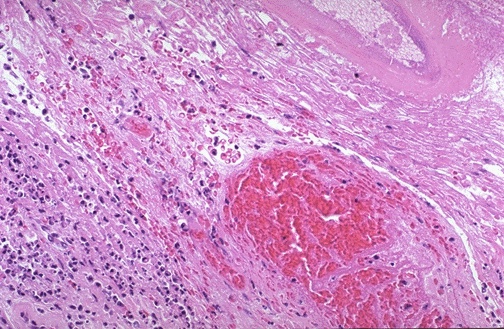

Inflammation and hemorrhage is seen here in the region of a ruptured varix of the esophagus.